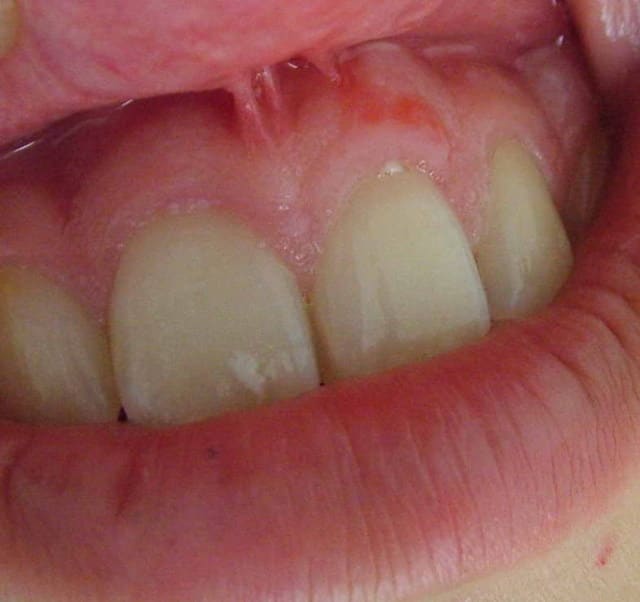

Suite à une chute de cheval remontant à avril 2004, une jeune patiente présente une sorte de cicatrice gingivale à la verticale de 21.

Pensez-vous qu'elle disparaîtra avec le temps ?

Sinon, que préconisez-vous ?

cicatrice tres discrete cher Bx, j'ai honte mais je ne l'ai pas vue!.......

je pense comme patvat qu'elle ne disparaîtra pas, et je pense comme athos qu'elle est à peine visible, à moins que ton patient ait un sourire de cheval, précisément.